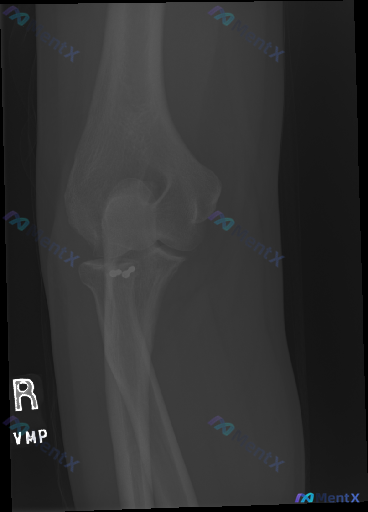

这张右肘关节斜位X光,第一眼容易漏看的高密度影是什么?

整理到一张右肘关节斜位X光的影像资料,先把关键信息放出来: - 骨性结构:肱骨远端、尺桡骨近端骨皮质连续,关节对合良好,无明确骨折/脱位,脂肪垫征阴性 - 异常发现:在桡骨颈近端内侧、靠近尺骨冠突的区域,有两个边缘锐利、密度明显高于骨骼的类圆形高密度影,有金属伪影特征 - 周围软组织无明显肿胀 现在...